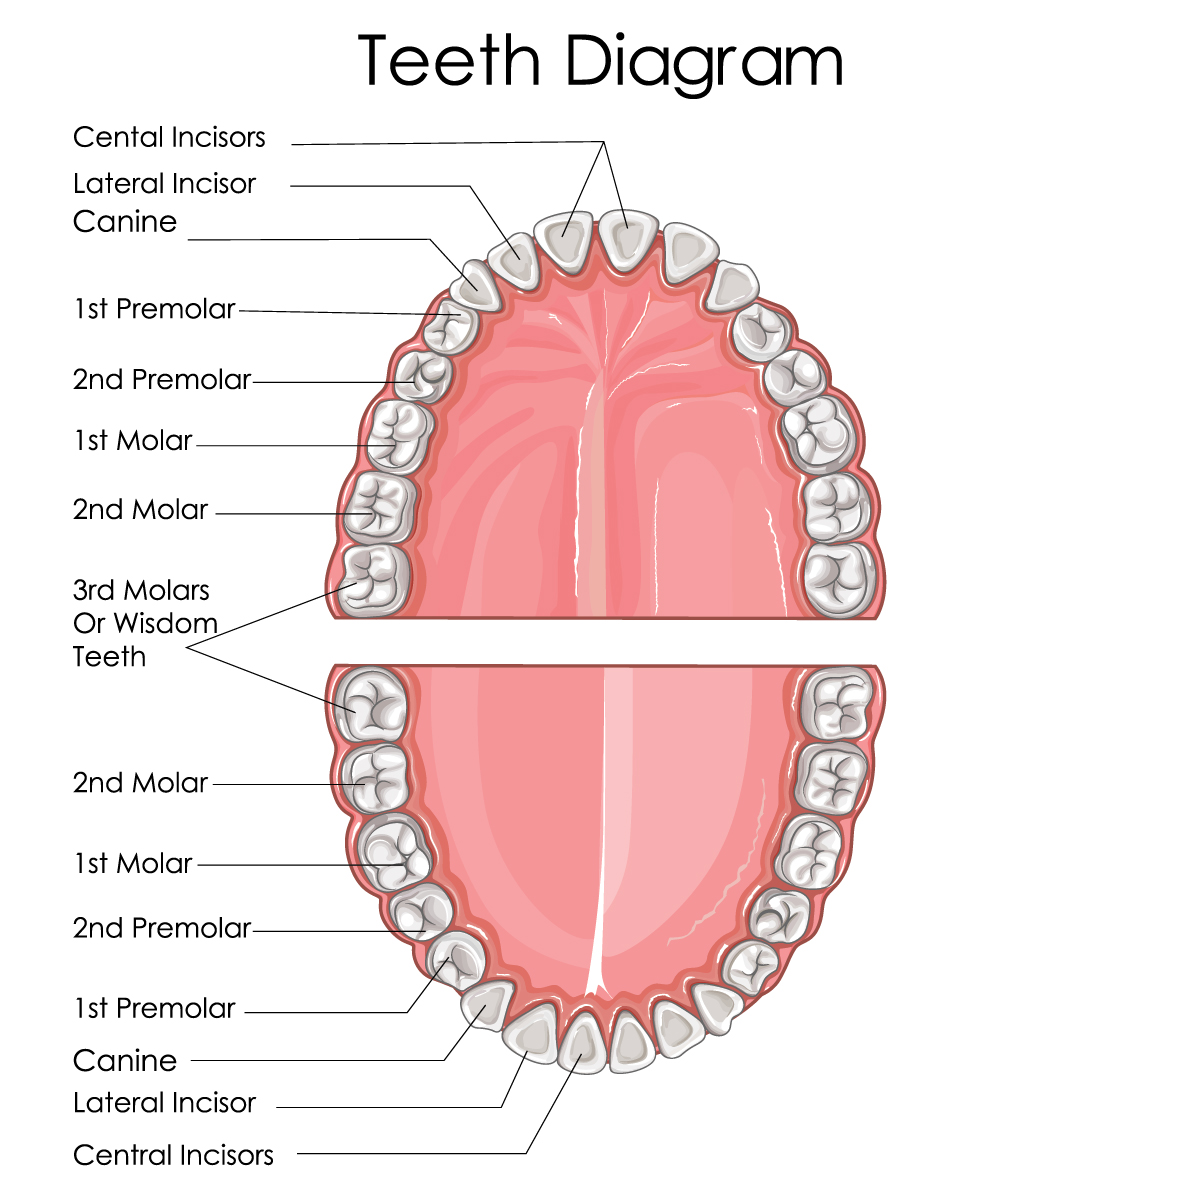

Human teeth are programmed to grow and erupt (come through the gums) in a specific order. Hanley says the first primary tooth erupts around 6 months old, while the first permanent tooth doesn’t arrive until close to 6 years of age. This eruption process continues until the third molars show up at around 17 to 21 years of age.

Most humans develop 20 primary teeth and 32 permanent teeth.

Horses and humans both grow four different types of teeth: incisors, cuspids (canines), bicuspids (premolars), and molars.

Human teeth are also rooted in the alveolar bone, according to Hanley. In humans, this bone forms our upper and lower jaw. Human teeth have two different components: the crown and the root.

Humans have brachydont teeth, meaning low-crowned teeth that don’t continuously erupt. The crown is the portion of the tooth seen when a person smiles. Human crowns are capped with enamel, the hardest part of the tooth.

“Enamel provides a hard, durable chewing surface that is resistant to deformation,” says Hanley.

Underneath the enamel is a layer of dentin, which recognizes sensitivity.

Finally, under the dentin lies the vascular core of the tooth where the dental pulp resides. This is where the blood supply, nerve endings and other internal components of the tooth are located.

The second component of human teeth, the root, makes up the lower part of the tooth and is generally below the gums. Cementum covers the outer part of the root, followed by a layer of dentin. The dentin surrounds the inner pulp canal that leads up into the crown of the tooth, according to Hanley.